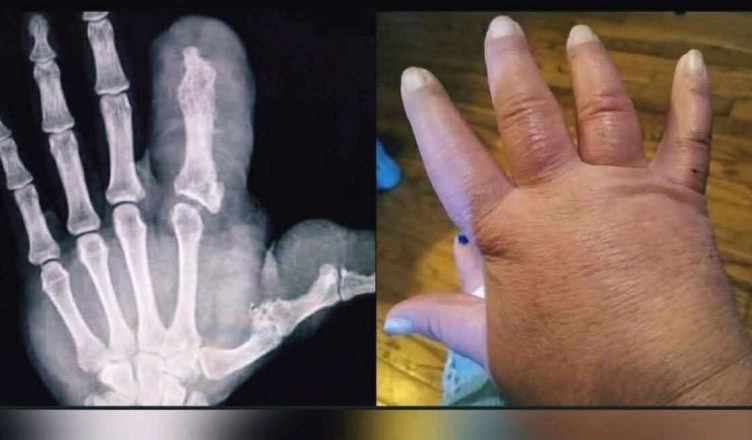

Depuis sa naissance, son pouce avait grandi plus vite que le reste de sa main. Au début, cela paraissait anodin, une petite bizarrerie d’enfance dont on parlait avec le sourire. Mais année après année, la peau se tendit, l’ongle devint comme une petite coquille, et la main perdit sa forme familière. Les médecins attribuèrent ce phénomène à un mot qui semblait presque étranger : macrodactylie. Cela expliquait tout et rien à la fois.

Quand on lui a proposé l’opération, sa mère tremblait plus que sa fille. « On va juste ralentir un peu la croissance, d’accord ? » dit doucement le médecin, comme s’il expliquait quelque chose à une fleur vivante. Après l’anesthésie, il y eut la douleur, une sensation de brûlure, puis des bandages comme un cocon, et un espoir discret : peut-être que maintenant tout allait s’arrêter. Mais le doigt recommença à pousser.